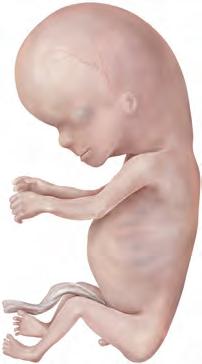

Stadi 21-23 (settimana 8) Gli stadi dell’ultima settimana del periodo embrionale sono caratterizzati dal differenziamento dei tipici caratteri umani. La testa risulta meno curvata e si sviluppa il collo (D10). Si sviluppano inoltre l’orecchio esterno (D11) e le palpebre (D12). Gli arti si allungano, le dita (D13) sono formate da più falangi e risultano reciprocamente separate. Si sviluppano le dita dei piedi e ha inizio l’ossificazione condrale. In corrispondenza dei genitali esterni si manifestano specifiche differenze di sesso.

Periodo fetale (generalità)

Il periodo fetale è caratterizzato dal differenziamento e dalla maturazione degli apparati e dal rapido accrescimento del feto. Le dimensioni corporee del feto vengono determinate in base alla lunghezza vertice del cranio-coccige (LVC) (in posizione seduta) o in base alla lunghezza vertice del cranio-tallone (LVT) (con gambe distese) e vengono espresse in mm o in cm. Per l’esatta determinazione delle dimensioni e dell’età, in base all’esame ecografico è inoltre possibile misurare il diametro biparietale (DBP) del cranio e la lunghezza del femore. All’inizio della nona settimana il feto pesa circa 10 grammi, mentre al termine del periodo fetale il suo peso ammonta a circa 3400 grammi.

I principali cambiamenti del feto vengono rilevati a distanza di un mese. In questo caso si osserva soprattutto l’accrescimento quasi sproporzionato della testa rispetto al tronco e agli arti. Infatti, all’inizio del periodo fetale la testa misura quasi metà della lunghezza totale del feto, mentre alla fine del periodo prenatale essa costituisce soltanto un quarto della lunghezza totale.

9a-12a settimana A causa del rapido accrescimento dimensionale, entro la fine della 12a settimana la LVC raddoppia. In rapporto al tronco, il collo e gli arti, in particolare quelli superiori, aumentano (A). La faccia assume tratti maggiormente caratteristici, poiché gli occhi, inizialmente collocati su un piano piuttosto laterale, migrano in direzione ventrale e gli orecchi assumono la loro posizione definitiva ai lati della testa. Le palpebre aderiscono le une alle altre, chiudendo la rima palpebrale. Entro l’11a-12a settimana, le anse intestinali collocate nel cordone ombelicale si riportano nella cavità addominale ora più spaziosa. Nella 12a settimana ha luogo il definitivo differenziamento tra organi genitali esterni maschili e femminili.

13a-16a settimana Tale periodo è caratterizzato da un accrescimento estremamente rapido del tronco, del collo e degli arti. La testa si solleva. Il corpo si copre di sottili peli, la lanugine, e il tipo di capigliatura diventa riconoscibile. L’ossificazione procede, cosicché nel feto di 16 settimane (B) le ossa sono riconoscibili in radiografia.